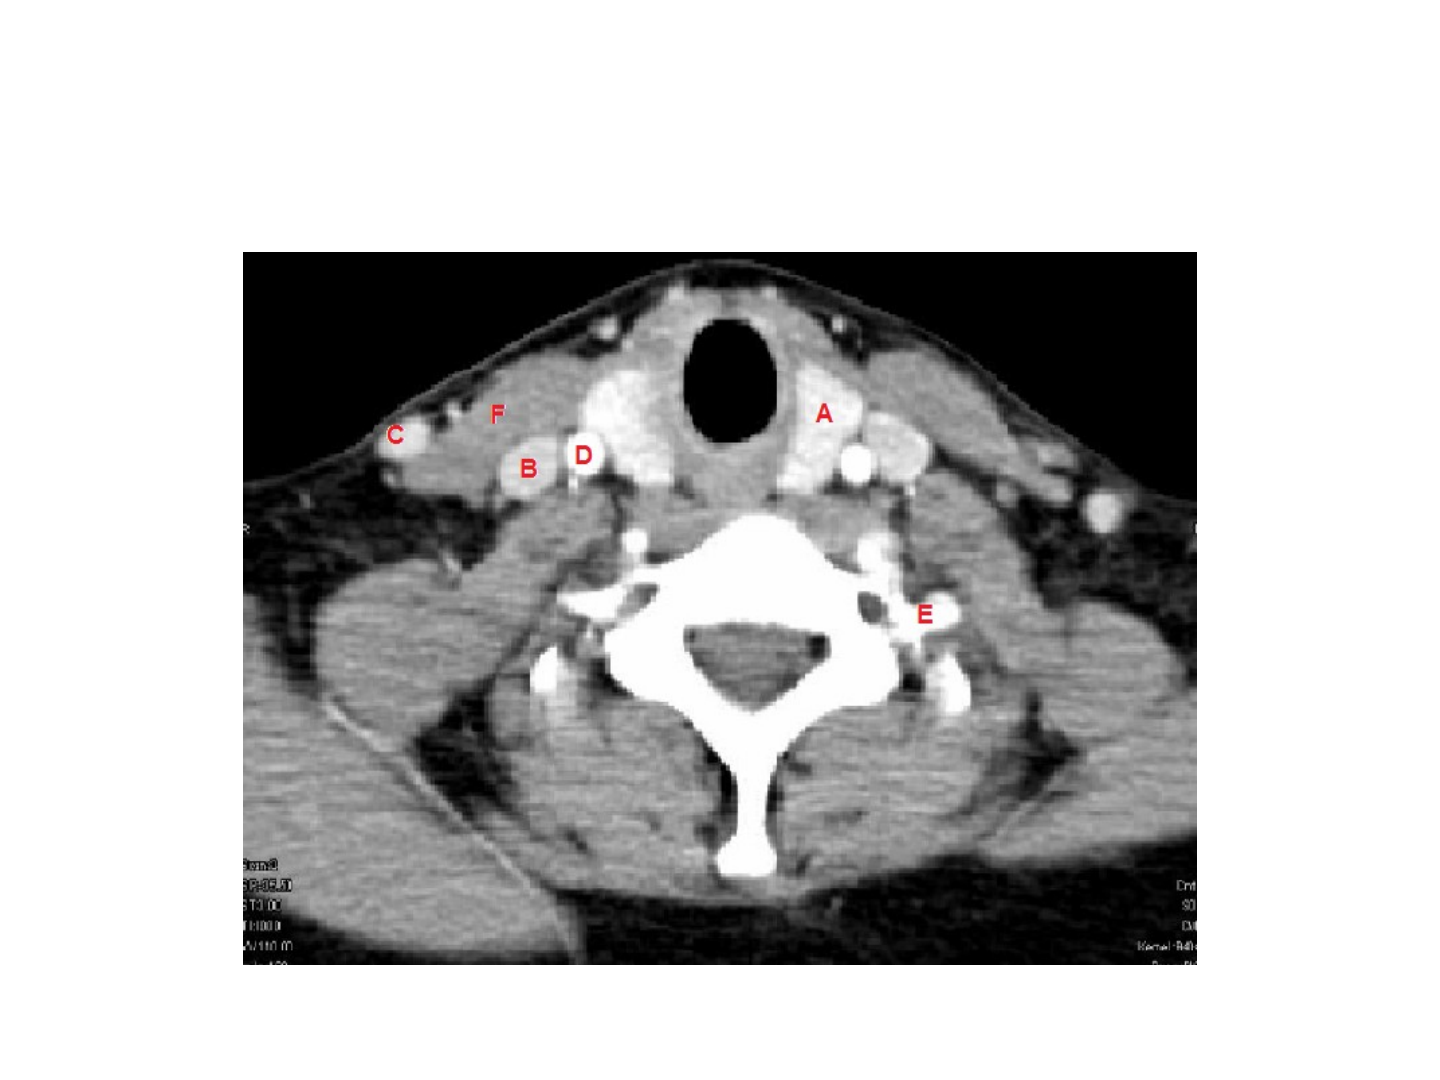

A-B-C-D-F: N

ombre

la es

tructura señalada.

E: Nombre el sect

or del hueso señalado.

A: lóbulo iz

quier

do de l

a glándula tir

oides.

B: V

ena yugular in

t

erna Der

echa.

C: V

ena yugular e

x

D: Art

eria Car

ótida Prim

itiv

a Der

E: Apófisis

tr

ans

ver

sa

iz

da.

F: Músculo E

CM.